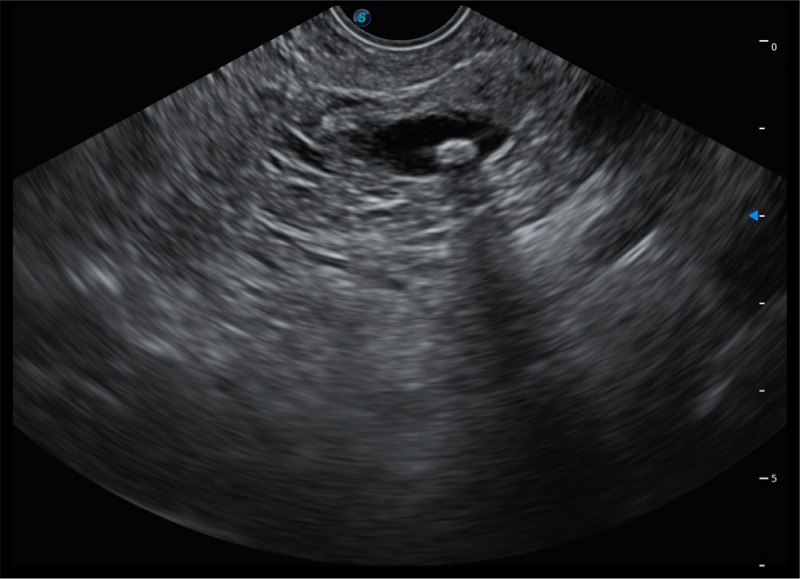

基于二十年的超声技术积累,九州酷游提供了最新一代的独立超声主机,在提供高质量图像的同时满足多学科使用。具备常见多普勒技术并提供弹性成像、声学造影等高端影像技术。新一代传感器具有更强的抗干扰能力并减少图像伪影。

150°超声扫描角度

4-12MHZ宽频输出